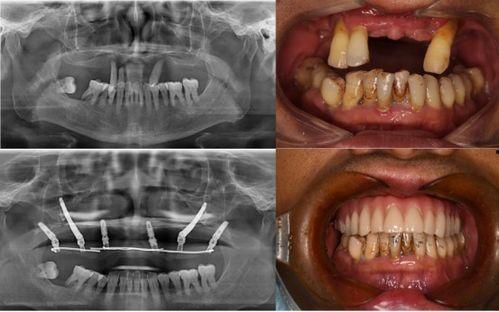

據患者們反映,他們在種植牙的過程中,遇到了種種問題。有的患者表示,醫生在手術過程中操作不規范,導致種植牙失敗;有的患者則抱怨,術后恢復期過長,而且效果并不理想。更有甚者,竟然出現了種植牙植入后,牙槽骨吸收的情況。

對于這起事件,口腔醫學專家也給出了自己的看法。他們認為,種植牙是一項高風險的手術,需要醫生具備豐富的經驗和專業的技術。而這家口腔醫院在種植牙過程中出現的問題,反映出我國口腔醫療行業在規范化、專業化方面還存在不少問題。